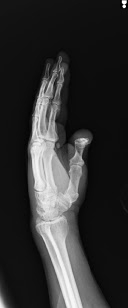

Clinical Images

X-RAY